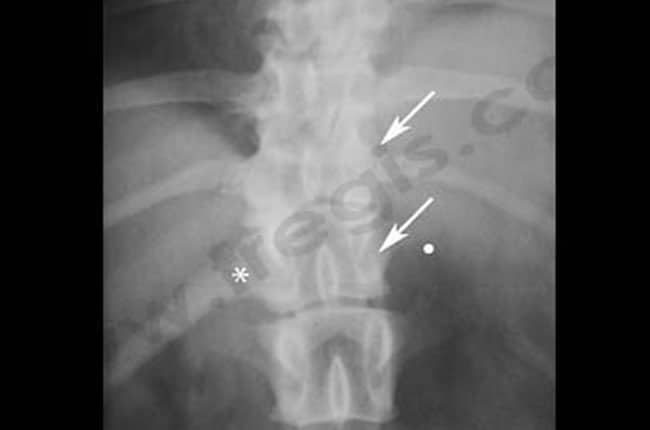

Chez le chien, le diagnostic d’hémivertèbre se fait grâce à un examen radiographique sous plusieurs incidences (face et profil).

Lorsque le chien présente des signes nerveux associés à ces malformations vertébrales, des examens d’imagerie plus poussés sont nécessaires afin d’évaluer le degré de compression. Les plus couramment prescrits sont une myélographie, un scanner, une myélo-tomodensitométrie ou une IRM.